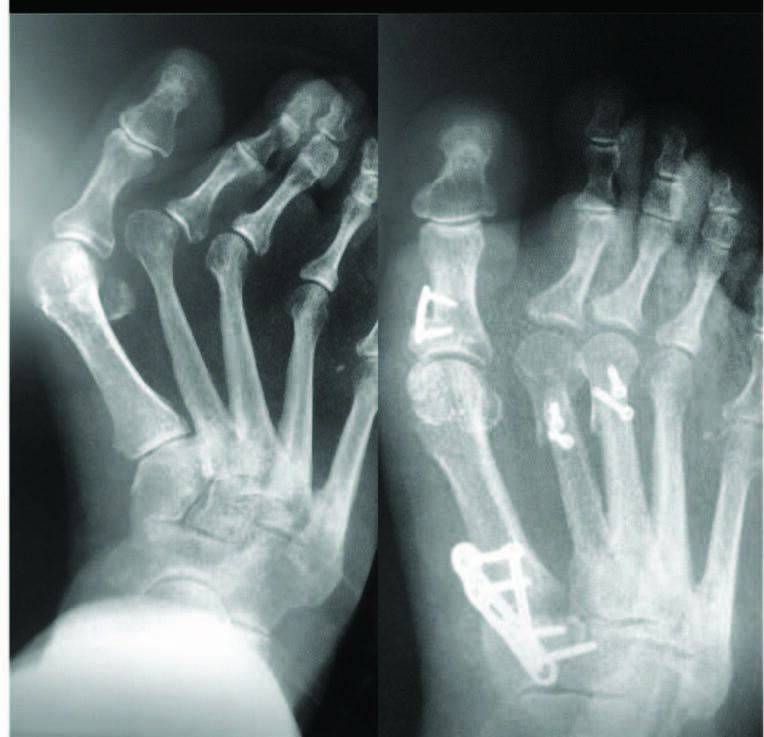

Management of Hallux Valgus in Metatarsus Adductus Foot and Ankle Clinics Foot Orthotics For Metatarsus Adductus Metatarsus adductus (ma) is the most common congenital deformity of the foot in newborns and is present in 1 to 2 babies per 1000 births. In this video interview, izak daizade, md, an orthopedic surgeon practicing in israel and the inventor, president, and director of unfo med ltd, discussed metatarsus adductus. For flexible metatarsus adductus, gentle stretching of the foot. Foot Orthotics For Metatarsus Adductus.

Management of Hallux Valgus in Metatarsus Adductus Foot and Ankle Clinics Foot Orthotics For Metatarsus Adductus Nonsurgical treatments such as serial casting, modified shoes (bebax shoe, ipos antiadductus shoe) and orthoses (wheaton brace, counter rotation system splint, denis brown bar, and fillauer bar) are widely used in this. There are various treatment approaches for the subjects with metatarsus adductus, including nonsurgical and surgical treatment. Metatarsus adductus primarily involves medial deviation of the forefoot on the hindfoot.. Foot Orthotics For Metatarsus Adductus.

Management of Hallux Valgus in Metatarsus Adductus Foot and Ankle Clinics Foot Orthotics For Metatarsus Adductus There are various treatment approaches for the subjects with metatarsus adductus, including nonsurgical and surgical treatment. For flexible metatarsus adductus, gentle stretching of the foot several times per day will help. Secondary characteristics include prominence of the 5th. Unlike casts, orthotic devices used to treat mta operate below the ankle to allow the joint to move freely, preventing stiffness. This. Foot Orthotics For Metatarsus Adductus.